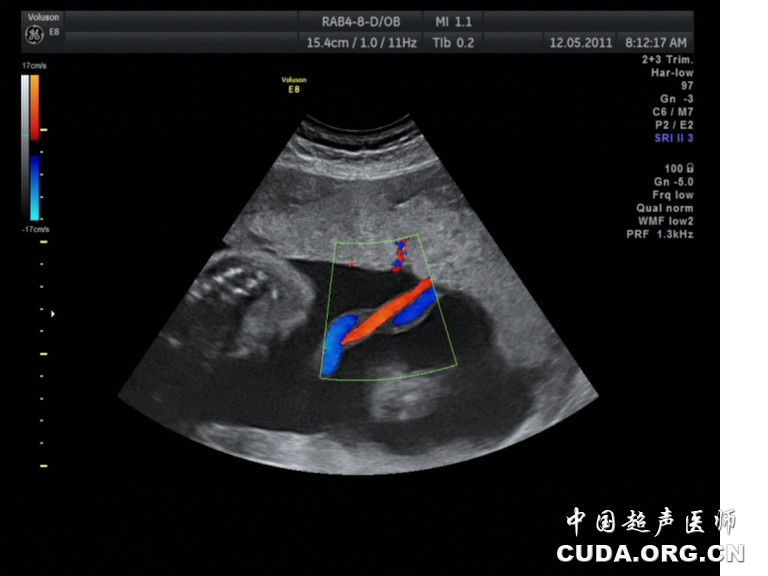

横向部分显示出一根粗大的蓝色脐静脉,二根细窄的桔红色的脐动脉并行

胎儿脐动脉血流